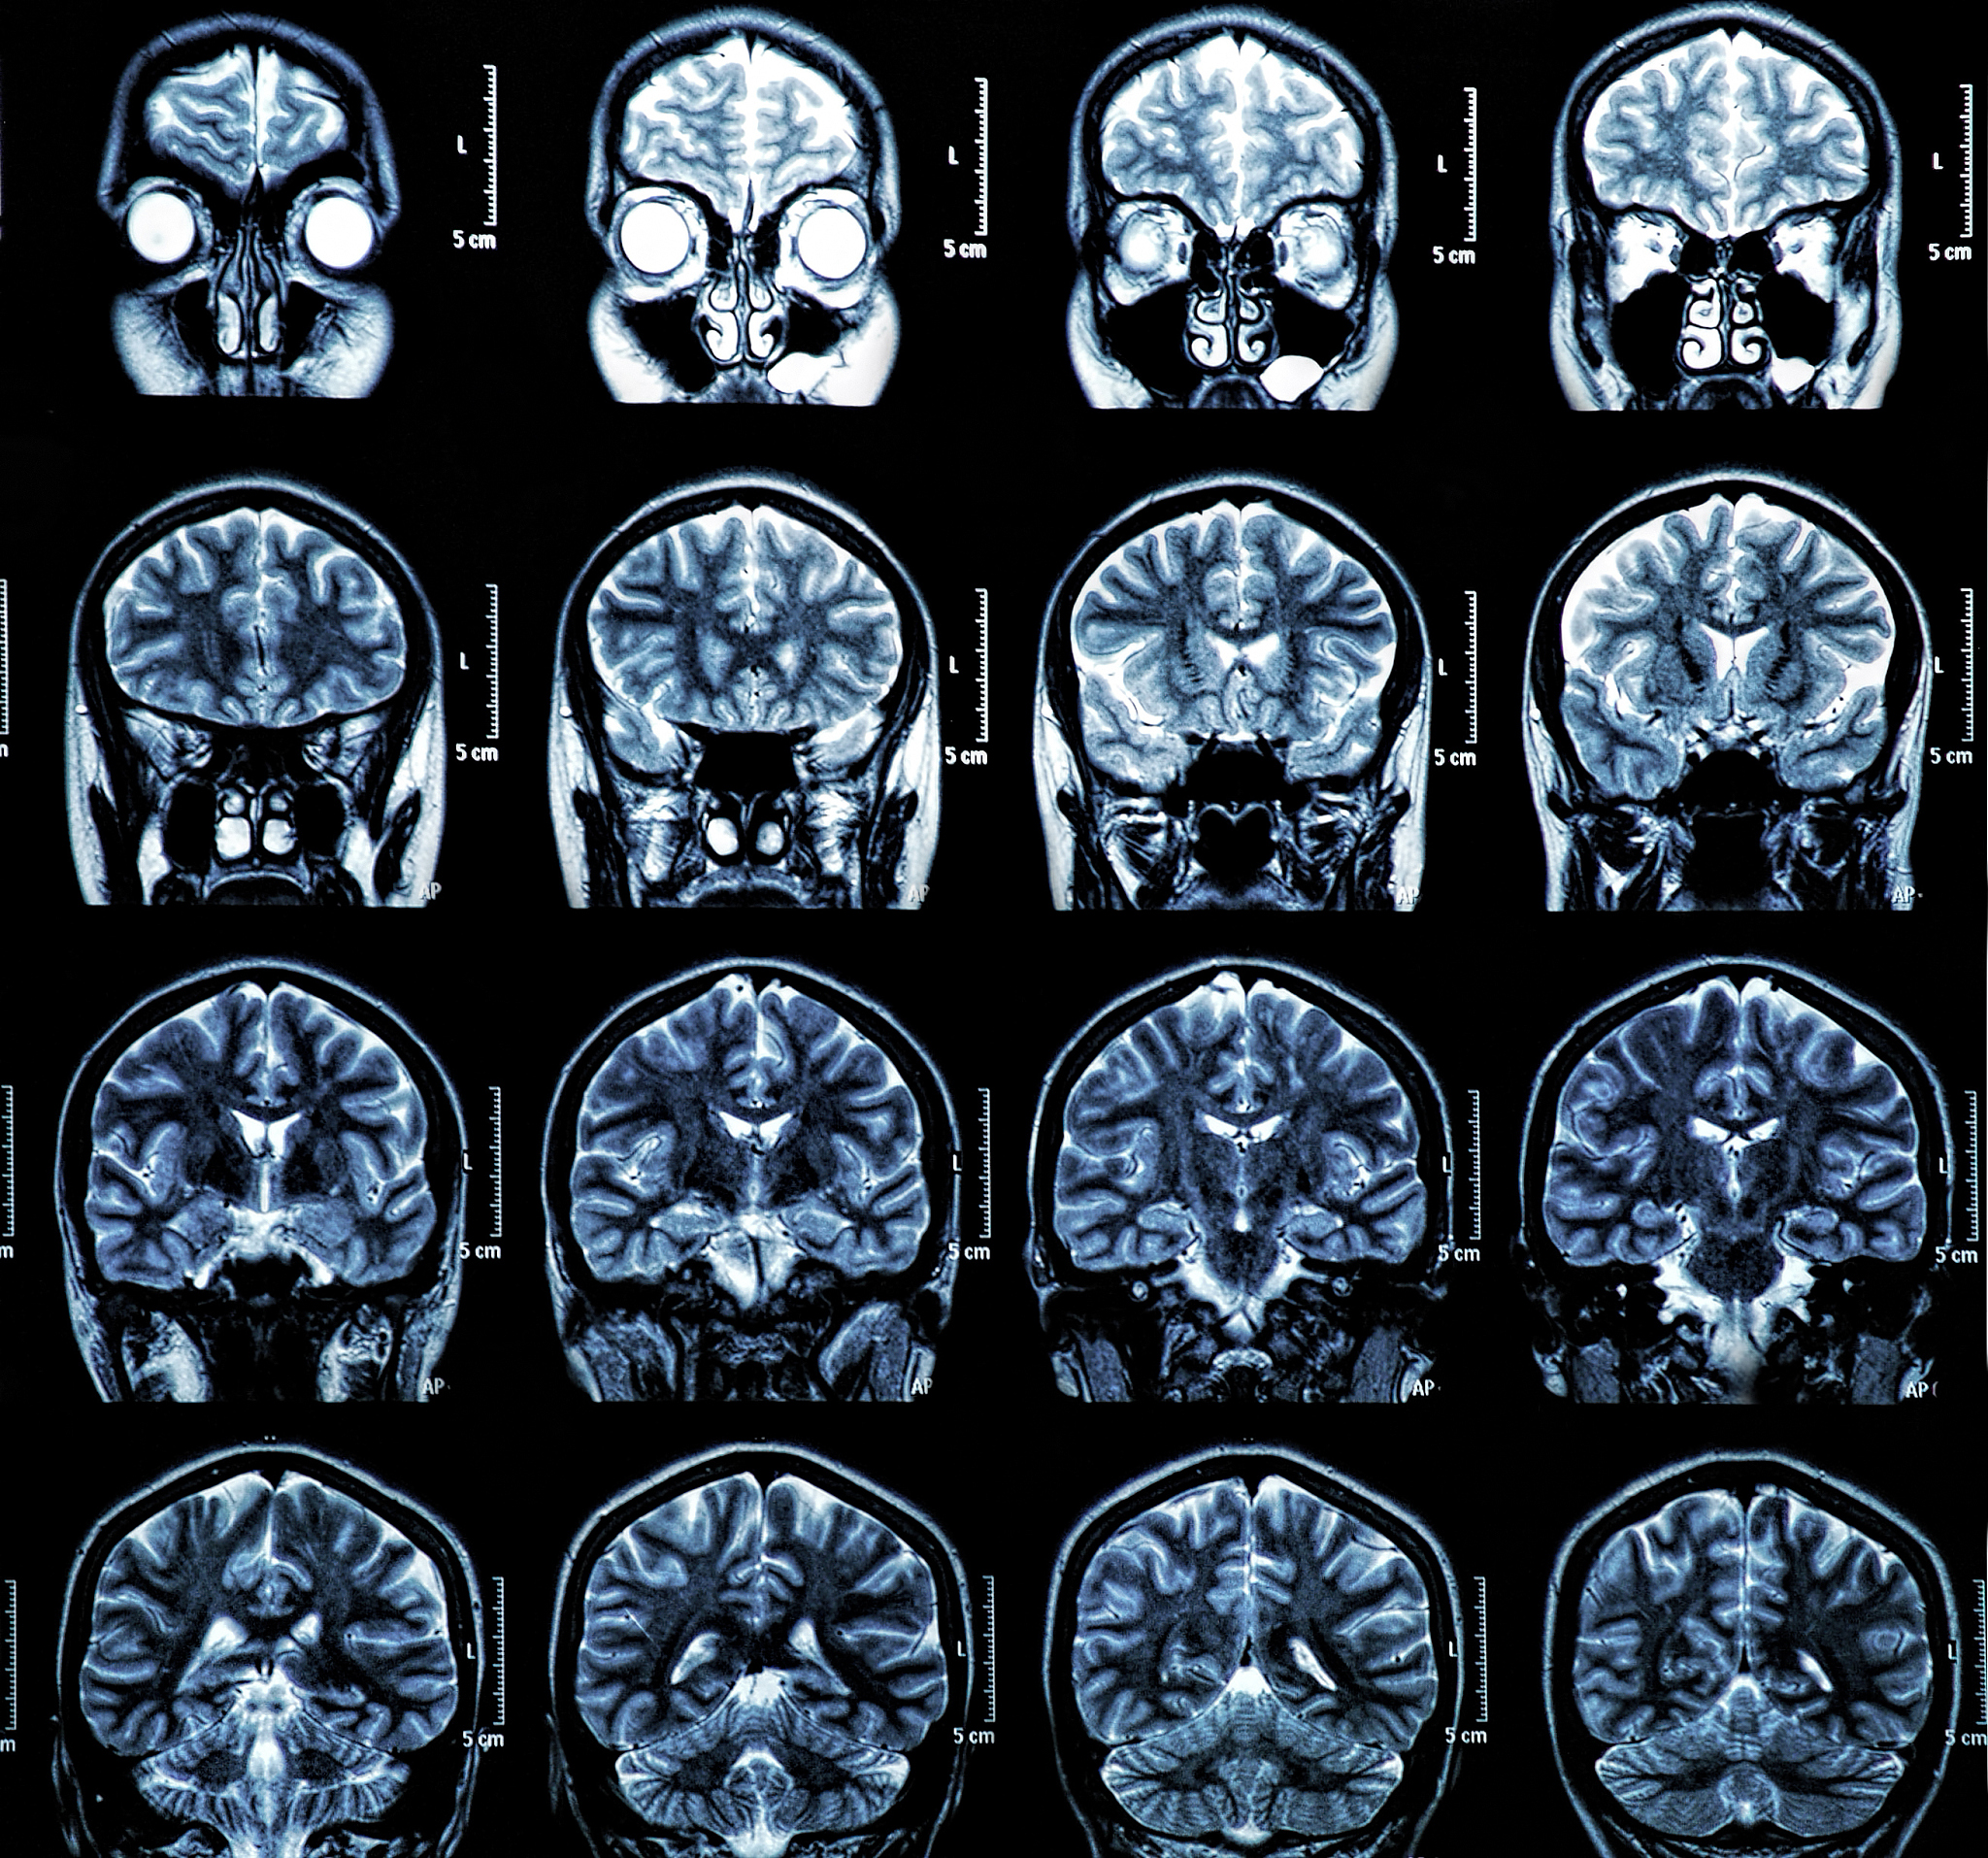

在使用合成磁共振技术应用于ADHD的研究方面,目前还存在许多未知的问题。在过去几年中,已经有一些研究表明,ADHD患者的小脑灰质存在异常,且'注意和执行控制网络'、'缺省模式网络'和'边缘区域'也存在异常。这些异常区域可能与ADHD症状的发生和发展有关。

合成磁共振技术在ADHD研究中的应用:现状与未来方向